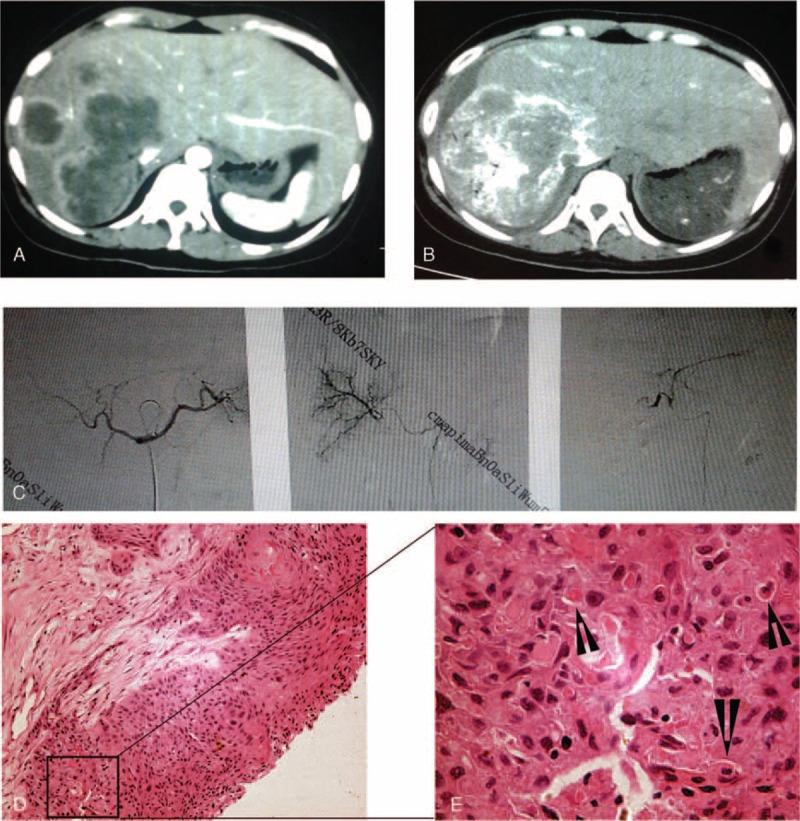

Primary squamous cell carcinoma (SCC) of liver is rare, and its prognosis is extremely poor. This study aims at reviewing the clinical data of all pathologically diagnosed liver cancer in our institute, and discussing the clinical presentation, diagnosis, treatment, and prognosis of our cases of SCC and the literatures reported previously. All the patients undergoing liver surgery or biopsy for liver cancers from 2002 to 2013 in our hospital were reviewed, and the liver specimens were examined pathologically. A literature search for case reports of primary SCC of liver published until December 31, 2014, was performed on PubMed, MEDLINE, Scopus Elsevier, Cochrane, and Google Scholar. The primitive data of the case reports were all included and analyzed if available. From January 2002 to October 2013, 2210 cases of liver cancer were diagnosed pathologically in our hospital. Among, 4 cases (0.2%) were diagnosed as primary SCC of liver. All were negative for hepatitis B infection, but present with liver cyst and/or hepatolithiasis. One patient underwent radical resection, but died of tumor recurrence 18 months postoperatively. One patient received transcatheter arterial chemoembolization and 1 patient received laparotomy and alcohol injection, but died 9 and 4 months after surgery, respectively. The last patient received only biopsy and supportive treatment, and finally died of tumor metastasis 6 months later. From 1970 to 2014, 31 cases of primary liver SCC have been published in English previously. Thirty one cases and the 4 cases in the present study were included. The average age of the patients were 54 years (range 18-83), with a male to female ratio of 19:16. Twenty patients had liver cysts, 7 had bile duct stones, and 2 cases had both. Patients undergoing radical surgery had better prognosis than those undergoing palliative treatments (median survival 17 vs 5 months, P = 0.005, log-rank test). Patients with liver cysts seemed to have worse prognosis than those with bile duct stones (median survival 7 vs 18 months, P = 0.090, log-rank test). Primary liver SCC seems to be mostly originated from liver cyst or hepatolithiasis. Radical surgery should be firstly recommended, although the prognosis might be unfavorable.

原发性肝癌(SCC)极为罕见,其预后极差。本研究旨在回顾我院所有经病理诊断的肝癌临床资料,探讨我院原发性肝癌病例的临床表现、诊断、治疗及预后,并与既往报道的文献进行讨论。回顾了我院2002年至2013年期间所有因肝癌接受肝脏手术或活检的患者,并对肝脏标本进行了病理检查。在PubMed、MEDLINE、Scopus Elsevier、Cochrane和谷歌学术上检索截至2014年12月31日发表的原发性肝癌病例报告。如果有可用的病例报告原始数据,则全部纳入并进行分析。2002年1月至2013年10月,我院经病理诊断肝癌2210例。其中,4例(0.2%)被诊断为原发性肝癌。所有患者乙肝感染均为阴性,但均伴有肝囊肿和/或肝内胆管结石。1例患者接受了根治性切除,但术后18个月死于肿瘤复发。1例患者接受了经动脉化疗栓塞术,1例患者接受了剖腹手术及酒精注射,但分别于术后9个月和4个月死亡。最后1例患者仅接受了活检及支持治疗,最终于6个月后死于肿瘤转移。1970年至2014年,英文文献中此前已发表31例原发性肝癌病例。纳入了31例病例及本研究中的4例病例。患者平均年龄54岁(范围18 - 83岁),男女比例为19:16。20例患者有肝囊肿,7例有胆管结石,2例两者均有。接受根治性手术的患者预后优于接受姑息性治疗的患者(中位生存期17个月对5个月,P = 0.005,对数秩检验)。有肝囊肿的患者预后似乎比有胆管结石的患者差(中位生存期7个月对18个月,P = 0.090,对数秩检验)。原发性肝癌似乎大多起源于肝囊肿或肝内胆管结石。尽管预后可能不佳,但应首先推荐根治性手术。